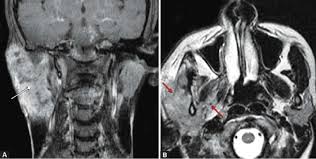

- High-grade MEC are characterized by:

- The invasion of adjacent structures

- Atypical, brisk mitoses

- Tumor necrosis

- Perineural invasion

- Cellular anaplasia

- Lymph node (40% to 50%) metastasis

- Distant metastases (33%).